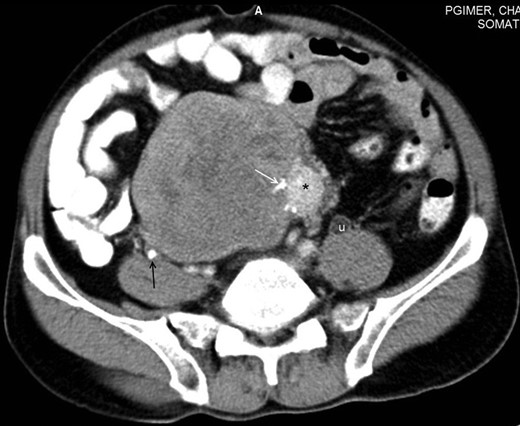

A 48-year-male patient presented with awareness of gradually increasing lower abdominal lump and abdominal discomfort for 8 months. There was no history of anorexia and weight loss. He was a non-smoker and non-alcoholic. His general physical examination was unremarkable with no clinical evidence of hepatic disease and adrenal or pituitary insufficiency. On abdominal examination, about 8 × 10 cm non-tender, hard, well-defined intra-abdominal lump was present in hypogastrium, which was extending into right iliac fossa, right lumbar and umbilical region for which the lower margin was not palpable. The lump was bimanually palpable on rectal examination. It was causing intra-luminal projection within rectum without any mucosal irregularity. His initial basic laboratory investigations which included hemogram, coagulogram, blood sugar, serum sodium, potassium, chloride, calcium, renal and liver function tests and urine analysis were within normal range. CECT abdomen (Figs 1 and 2) revealed a 20 × 15 × 7 cm heterogenous well-defined lobulated mass with calcification and areas of necrosis in the pre-sacral region and was extending superiorly up to the lower border of L3. It was indenting into the bladder anteriorly and rectum posteriorly, also abutting pelvic vessels but maintaining fat planes with all these structures. This mass was causing bilateral hydroureteronephrosis.

Axial section of contrast-enhanced CT of the abdomen reveals a large heterogeneously enhancing mass with a small hyperenhancing component (asterisk). Foci of calcification are noted within the lesion (white arrow). A few hypoenhancing areas are also seen within the lesion, which might represent necrosis or scar formation. Incidentally, a ureteric calculus is seen on the right side (black arrow). Dilated ureter (u) is noted on the left side due to compression by the mass lower down. Note that the fat planes with the bowel and the retroperitoneal vessels are maintained.